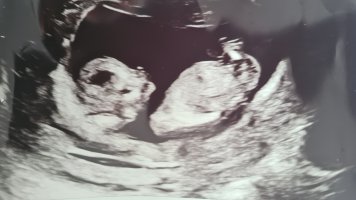

Ser ut som en jenteHåper det er nub på noen av disse (aner ikke hva man ser etter)

14+2 i dag, og navlestrengen lå mellom beina. Nurket sov og gjespet, ville ikke flytte på seg

ikke så vi noe nub heller